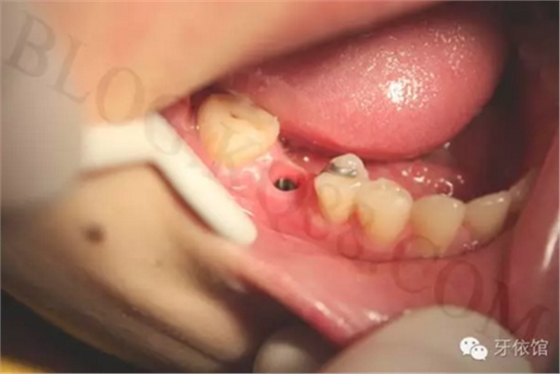

將基臺定位器和基臺同時在口內(nèi)就位,用手旋緊中央螺絲,試戴烤瓷牙,調(diào)整咬合,再用扭矩扳手旋緊中央螺絲。

粘冠。